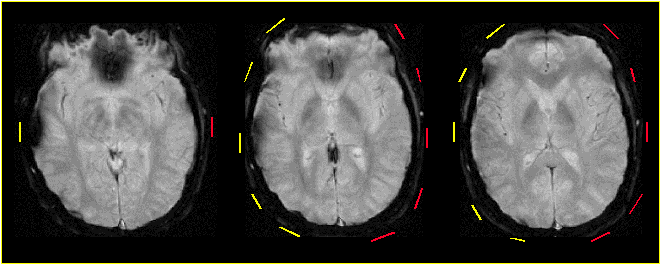

Figure 3. High resolution EPI of a subject with two types of EEG electrode assemblies applied

on the scalp. On the right side of the head, non-optimized electrode assemblies (silver/silver chloride electrodes

and carbon composition resistor; position shown in yellow) caused artifacts intruding into the cortex. Optimized

electrode assemblies (gold electrodes, cermet film resistors; position shown in red) used on equivalent positions

on the left side of the head did not compromise the cortical signal.